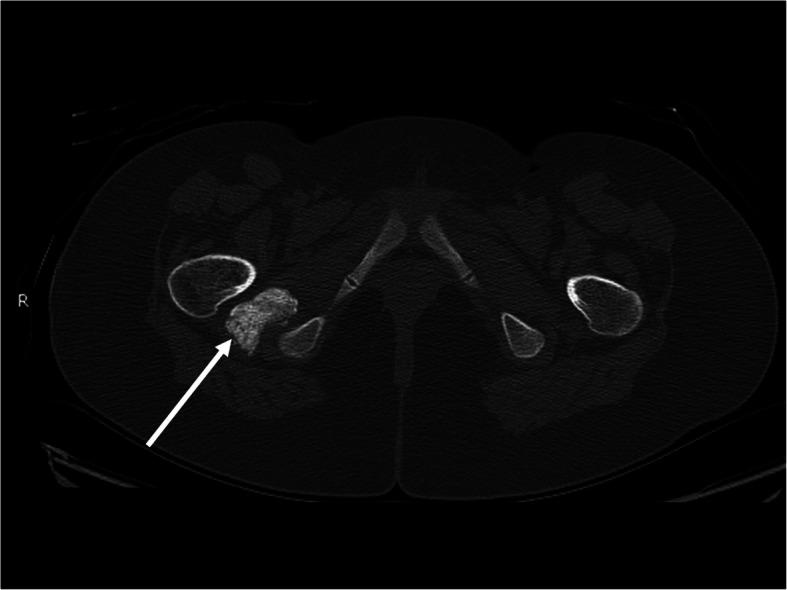

We describe the case of a 13 year-old girl with overlap syndrome with features of juvenile dermatomyositis and systemic lupus erythematosus. After 22 months of extensive immunosuppressive therapy, including monthly IVIG and Rituximab, she continued to have pain and weakness of the lower extremities. A CT scan was performed which showed significant multifocal soft tissue calcifications of the pelvis. She was started on treatment with oral alendronate with the goal of improving her calcinosis and improving her symptoms. After several months of therapy, our patient reported subjective improvement of her lower extremity pain and weakness, as well as complete resolution of abnormalities previously seen on physical examination. A repeat CT scan of the pelvis was performed after 11 months of therapy and demonstrated complete resolution of the previously seen calcinosis.

我们描述了一名13岁女孩的病例,她患有重叠综合征,具有幼年皮肌炎和系统性红斑狼疮的特征。在进行了22个月的广泛免疫抑制治疗后,包括每月静脉注射免疫球蛋白和利妥昔单抗,她的下肢仍持续疼痛和无力。进行了CT扫描,结果显示骨盆有明显的多灶性软组织钙化。她开始接受口服阿仑膦酸钠治疗,目的是改善她的皮肤钙化并缓解症状。经过几个月的治疗,我们的患者报告下肢疼痛和无力主观上有所改善,并且之前体格检查中发现的异常完全消失。治疗11个月后对骨盆进行了重复CT扫描,结果显示之前所见的皮肤钙化完全消失。